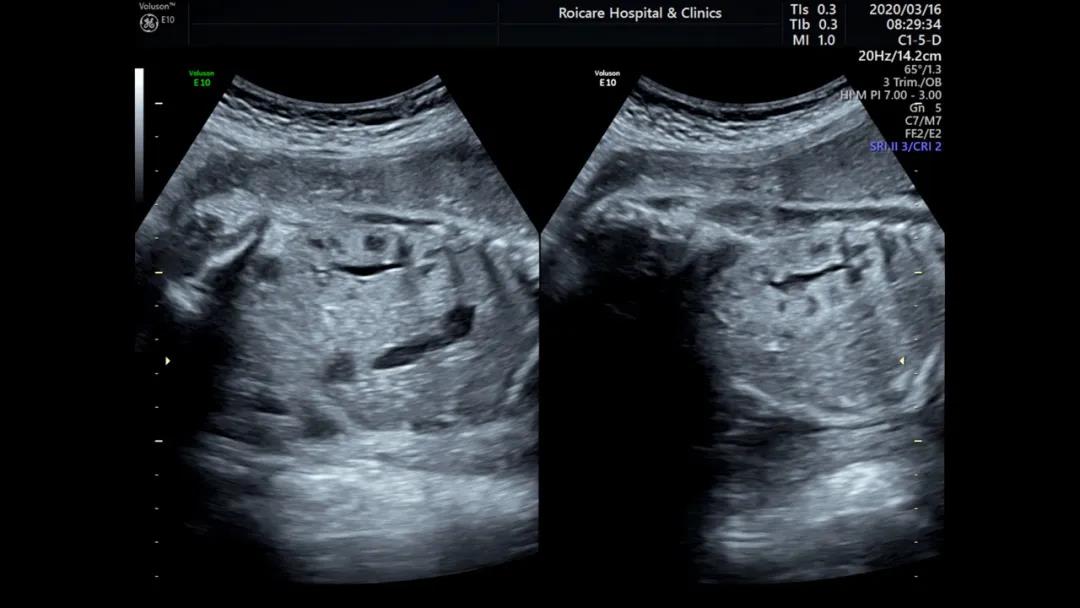

5.肝脏强回声

肝脏的强回声较为少见,可位于肝表面、肝实质内或肝内血管内。位于肝表面的强回声常与胎粪性腹膜炎有关。肝实质内的强回声与缺血坏死、出血、感染等有关,而肝血管内强回声可能与肝内静脉或脐静脉内血栓形成有关。还有就是肝脏的肿瘤可能也存在瘤体内的强回声。

出现肝内强回声时需要排除是否其他器官存在强回声,单纯的肝内强回声出生后可自行消失,除外染色体异常、感染等因素,往往预后良好。